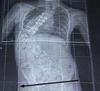

See how a lift in the shoe would have reduced the curve?

Incredibly important with a scoliosis is whether a lift in your shoe would lessen the curve; has anyone checked the height of your iliac crests?

Lifts are complex, usually reducing the curvature, but sometimes balancing the pelvis but increase the Cobb's angle. It needs to be carefully assessed.